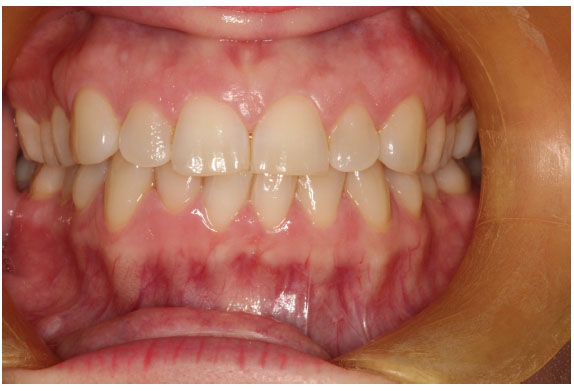

At first glance this mouth presents with a perfectly healthy set of teeth. The aesthetics are good. The soft tissue looks healthy and sound. It would appear to be a picture of health. It is probable that to the patient his mouth teeth feel fine. He probably has no awareness of any restorative problems.